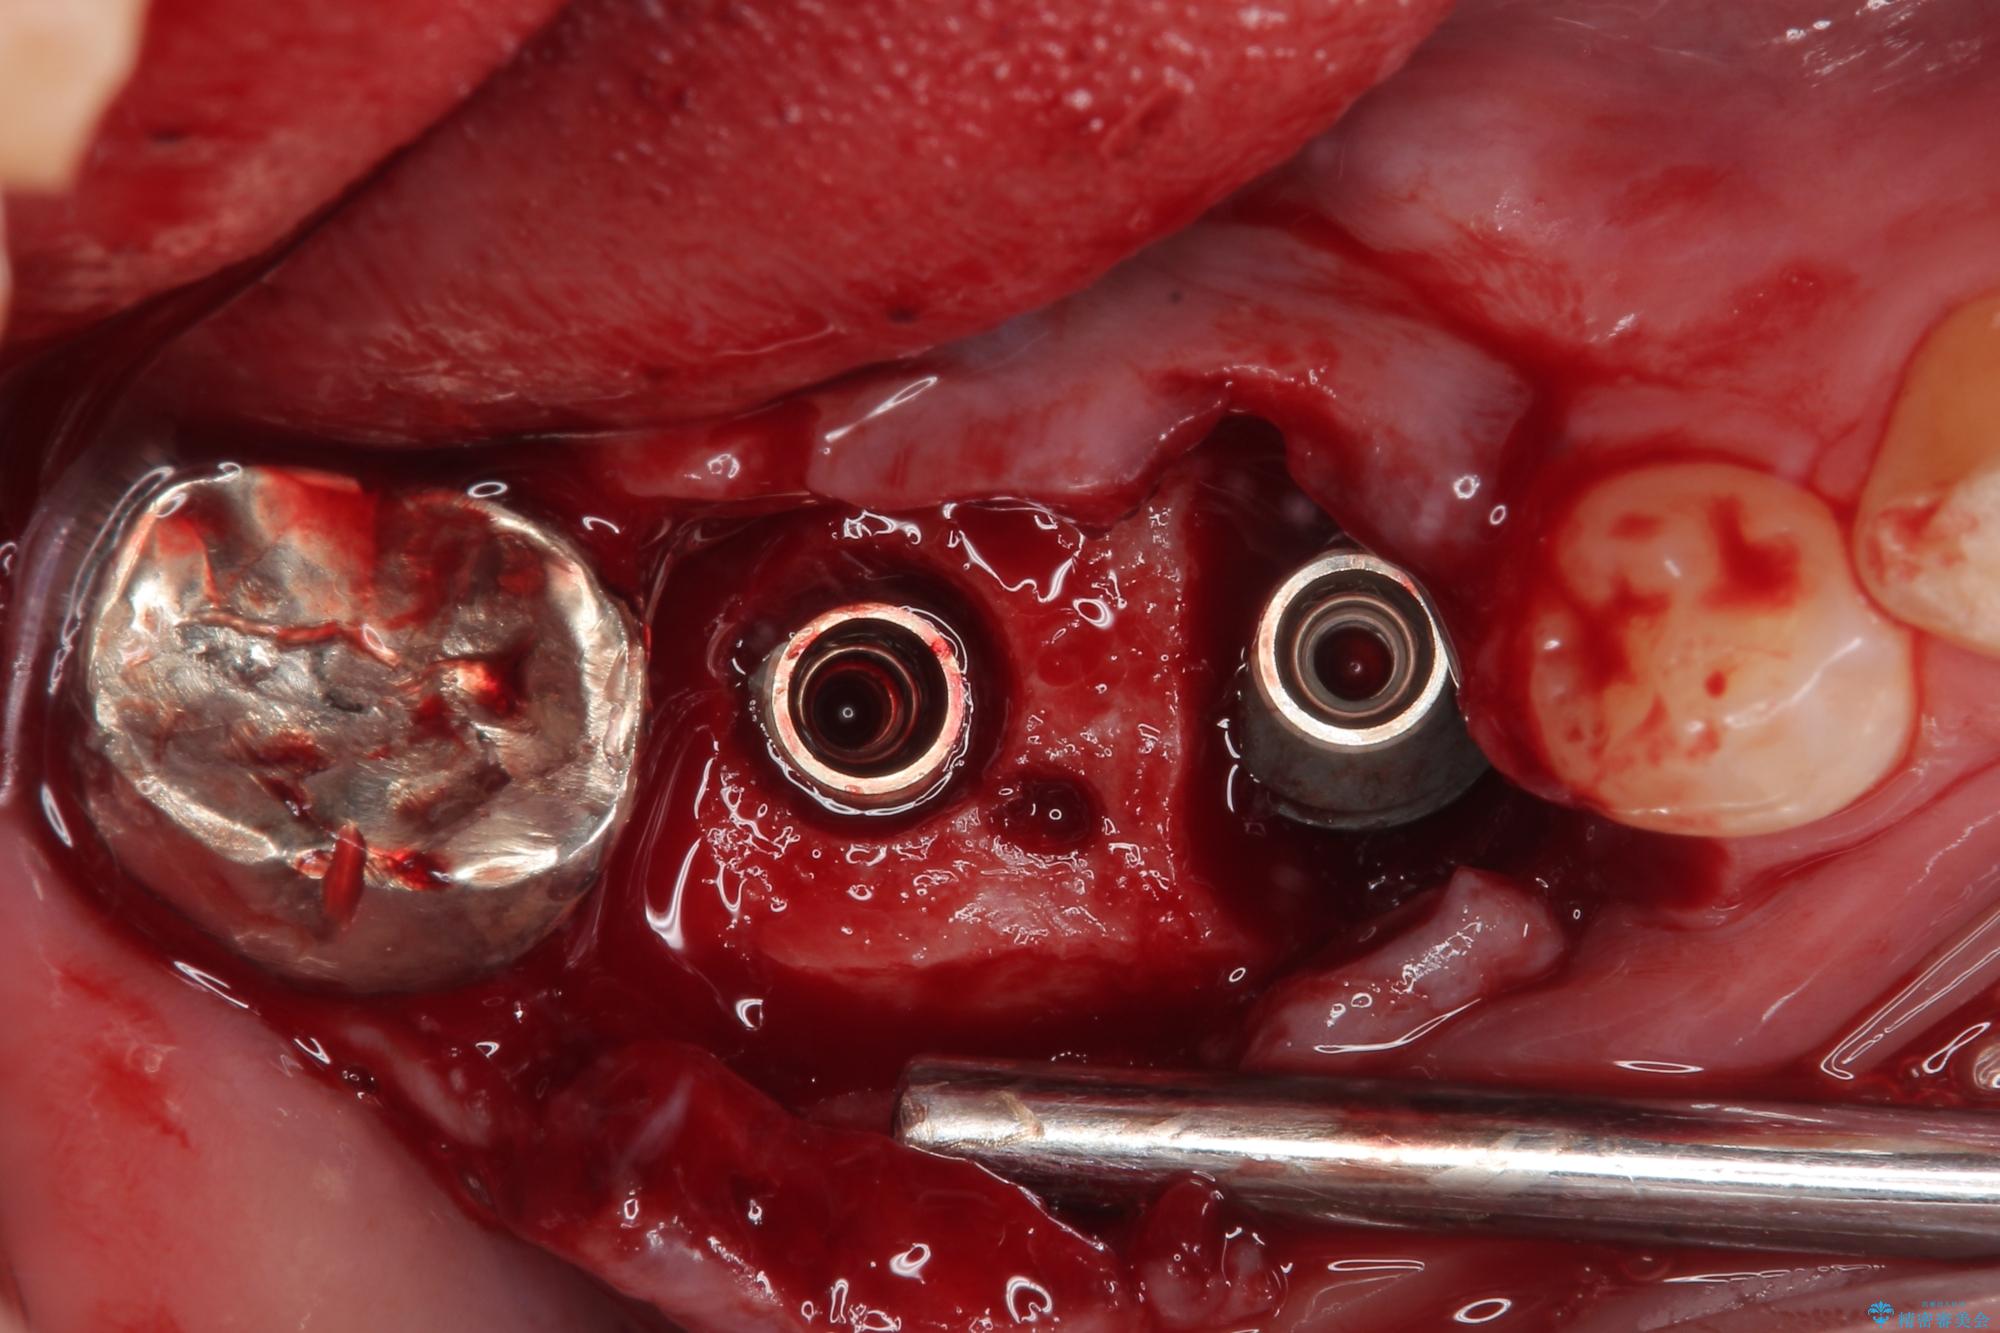

咬合力が非常に強い患者様であり、2歯欠損のブリッジ(しかも大臼歯は失活歯)は歯根破折のリスクが高すぎると判断し、抜歯部および欠損部に対して、インプラントによる補綴治療を行うこととしました。

抜歯即時埋入部と後方の欠損部は、即日荷重(インプラント埋入と同時に仮歯を装着すること)が可能な安定値が得られましたが、長い期間欠損した状態で過ごすと、欠損部に舌を押し当てる癖が発現してしまい、舌からの側方圧でインプラントが脱離するリスクが著しく高まってしまうため、即日荷重は行いませんでした。

おかげでインプラントは無事に生着し、僅か4ヶ月で治療を終えることができました。